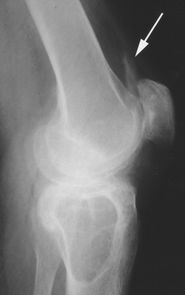

图1B -37岁女性,巨细胞瘤。股骨远端边缘(箭头)边缘不清。